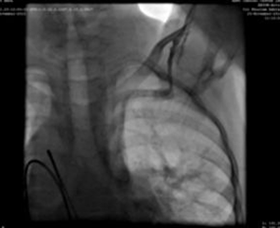

We used a 9F delivery sheath, which was advanced over and placed in the descending aorta over the super-stiff guidewire. A MemoPartTM cone shape PDA occluder 14/12 mm, was attached to the delivery cable and progressed across the delivery sheath. The placement of the occlude was proper with no residual flow.

Results

Surgical success, no serious intraoperative complications, echocardiography 24h after occlusion shows good placement, no residual shunt at the defect.